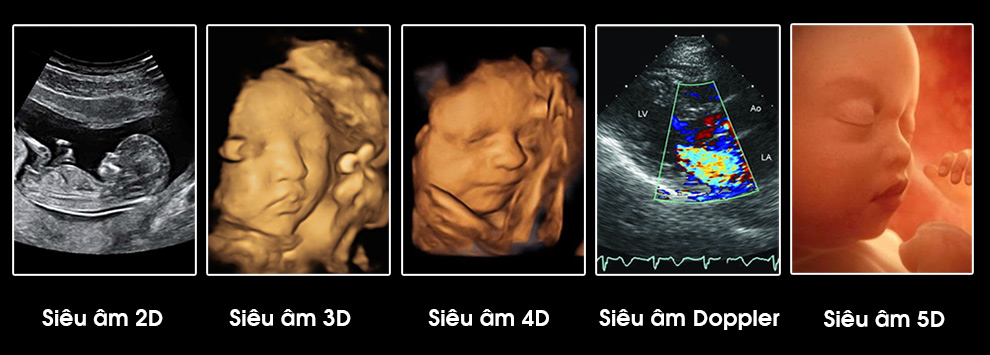

Siêu âm 2D (Hai chiều)

Mô tả: Là loại siêu âm cơ bản và phổ biến nhất, tạo hình ảnh mặt cắt ngang của cơ quan hoặc mô dưới dạng trắng đen. Đây là nền tảng cho mọi kỹ thuật siêu âm khác.

Siêu âm 3D và 4D

Mô tả: Siêu âm 3D tạo hình ảnh ba chiều rõ nét. Siêu âm 4Dlà siêu âm 3D động – cho phép quan sát hình ảnh theo thời gian thực.

Siêu âm 5D

Siêu âm 5D là công nghệ siêu âm tiên tiến, phát triển từ siêu âm 4D, giúp tái tạo hình ảnh thai nhi sống động, rõ nét với độ phân giải cao hơn và màu sắc chân thực hơn. Điểm đặc biệt của siêu âm 5D là khả năng tự động nhận diện và đo đạc các cấu trúc giải phẫu, hỗ trợ bác sĩ đánh giá sự phát triển của thai nhi một cách chính xác và nhanh chóng.

Siêu âm Doppler

Mô tả: Dựa vào hiệu ứng Doppler để khảo sát dòng chảy của máu trong lòng mạch. Hình ảnh Doppler có thể là màu hoặc đơn sắc, được tích hợp cùng siêu âm 2D.